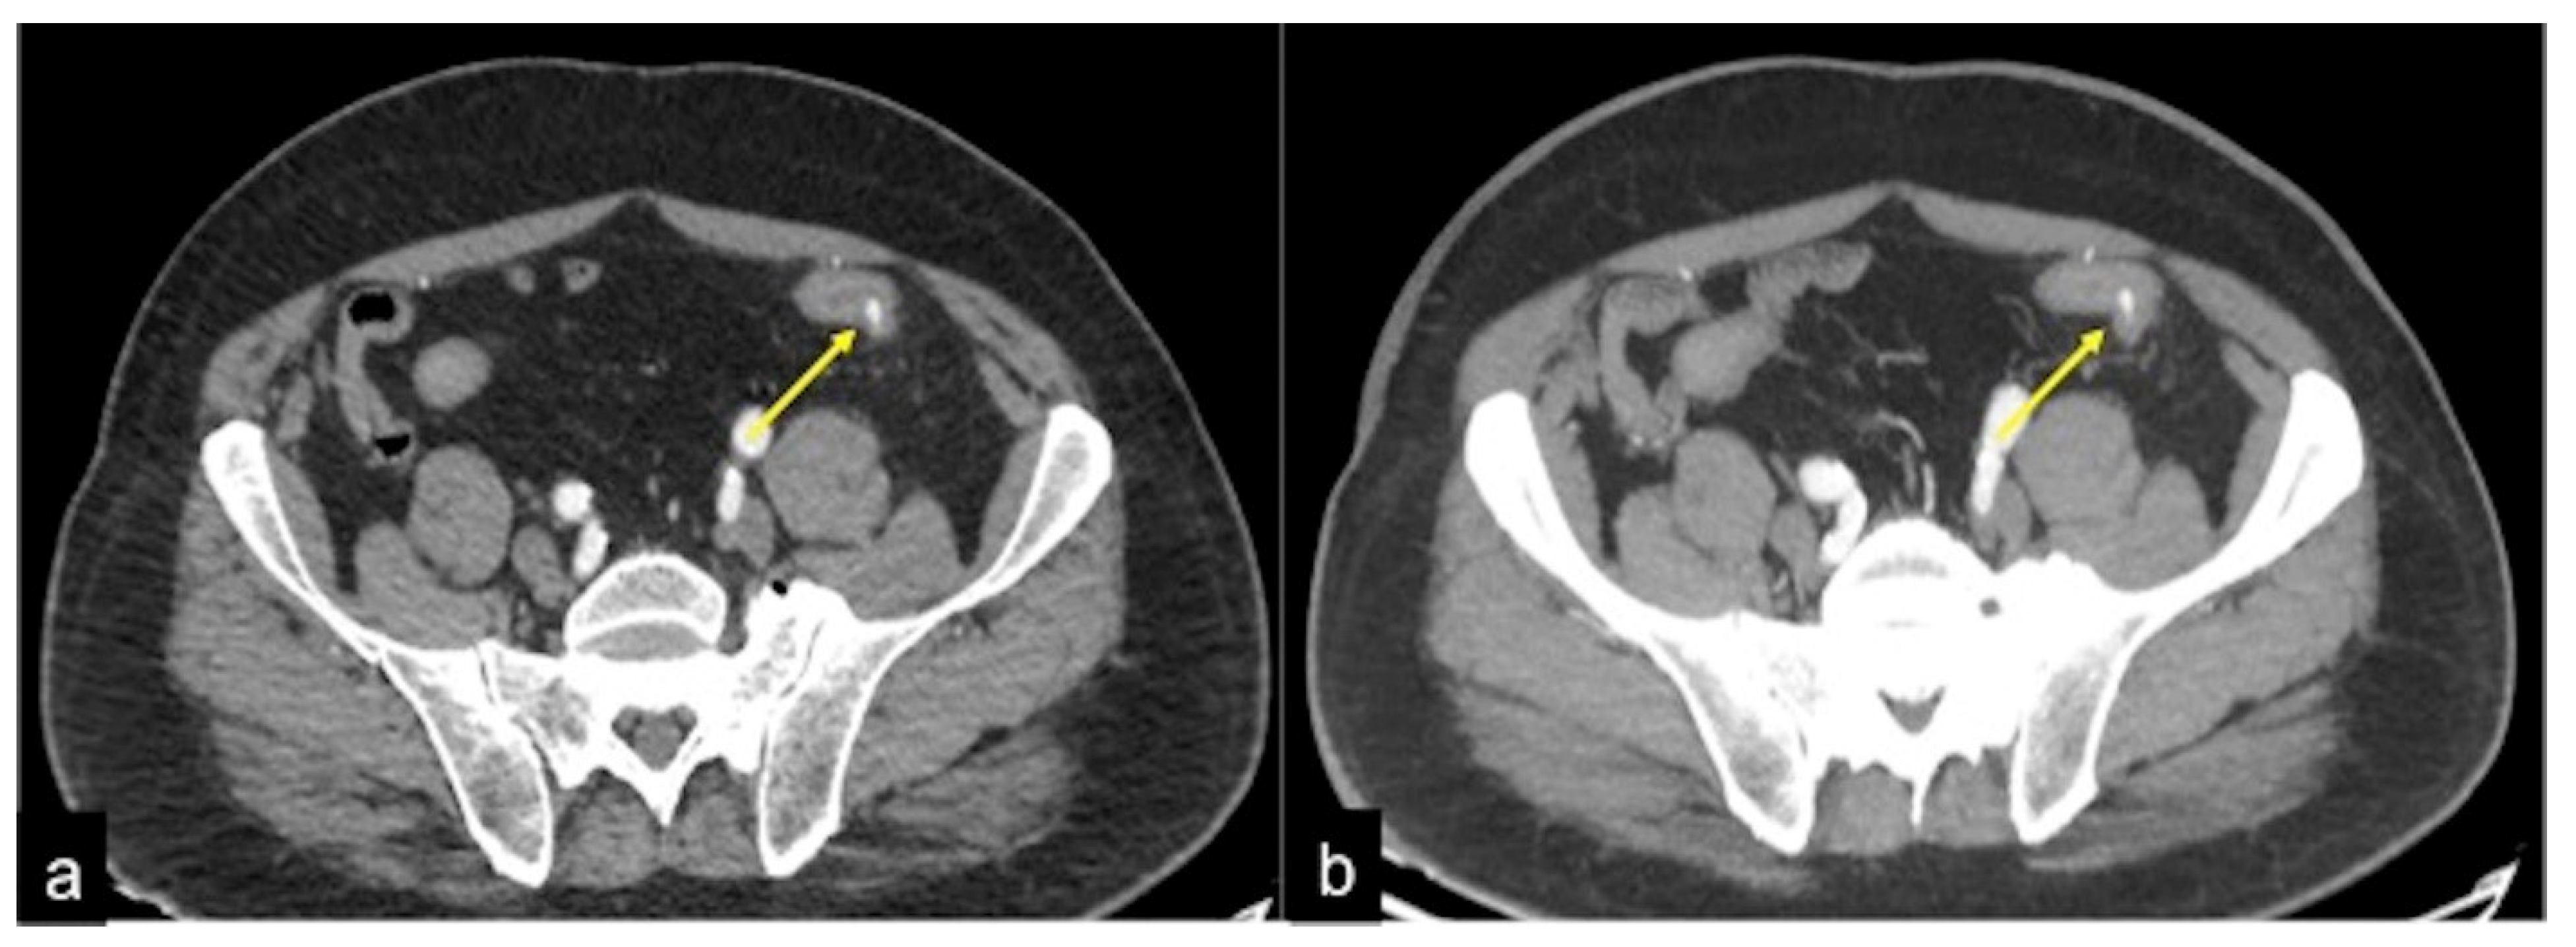

| Diverticulosis (Figure 33) | Asymptomatic or bleeding. | Protruding sacs where the vessels pass through the muscularis layer, between the mesenteric and antimesenteric taenia. |

| Angiodysplasia (Figure 5 and Figure 34) | Asymptomatic or bleeding. | Small hyperdense nodules within the intestinal wall, best defined in the portal phase of the study. |